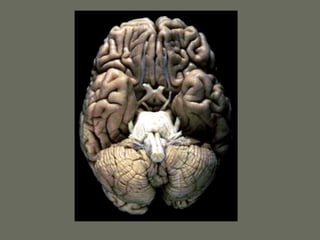

Parts of the Central Nervous

System

• 2 hemispheres

• Brainstem

• Cerebellum

• Spinal cord

Gyruses and sulci

• Each lobe is composed of gyruses

separated by sulci

• The topography can be defined by

histology, anatomical relationships or

function